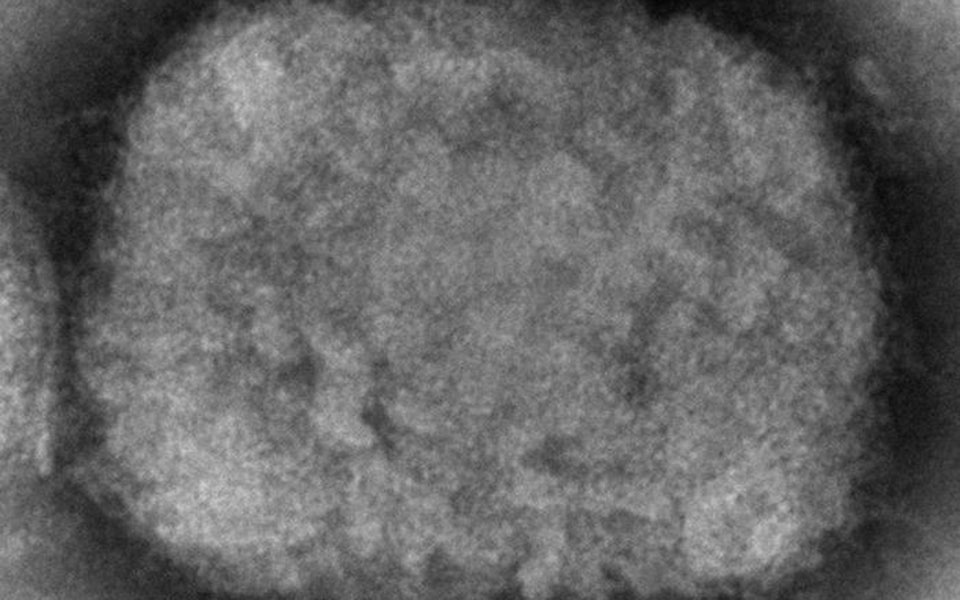

Όχι, Είναι μια ζωονόσος, ενδημική σε πολλές περιοχές της Αφρικής. Αν και ανιχνεύτηκε για πρώτη φορά σε πιθήκους το 1958 (εξ ου και η ονομασία του) μεταδίδεται ιδιαίτερα ανάμεσα σε τρωκτικά.